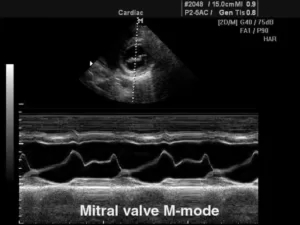

М-режим (отраженный импульсный режим)

M-mode («motion» — движение) — одномерная регистрация отраженного эхосигнала, применяющаяся в кардиологии для изучения сократительной способности миокарда, клапанного аппарата, оценки изменения размеров полостей в систолическую и диастолическую фазы.

В данном режиме оператор сканирует кардиальные структуры только вдоль одной оси. Информация о сигналах с различных глубин изображается в виде отметок различной яркости вдоль вертикальной линии на дисплее. Следующему зондированию соответствует другая линия, расположенная правее предыдущей. В ходе перемещения столбца с каждым новым сканированием записывается двухмерная М-эхограмма.

Существует несколько типов М-режима:

·      M-mode (стандартный): предполагает получение одномерного изображения;

9.jpg